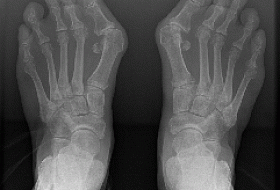

Hallux Valgus или почему растет косточка на большом пальце?

Большинство людей страдает от так называемой “косточки на большом пальце”. Основная проблема состоит в том, что многие из них начинают бороться с этим заболеванием, когда оно начинает доставлять им невыносимую боль при ходьбе, и в спокойном состоянии.